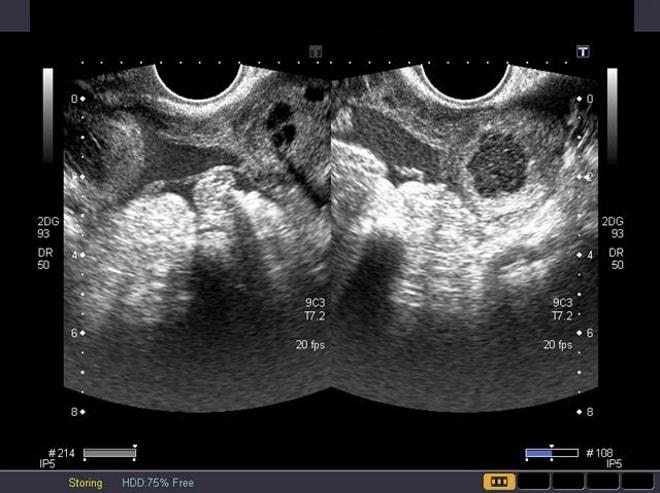

По мнению врачей, ранняя диагностика играет ключевую роль в предотвращении осложнений. Ультразвуковое исследование является основным методом для выявления кистозных образований, позволяя оценить их размер и структуру. Специалисты подчеркивают необходимость индивидуального подхода к каждому случаю, так как лечение может варьироваться от наблюдения до оперативного вмешательства в зависимости от клинической картины и состояния пациентки.

- ультразвуковое исследование;

Диагностика обычно включает ультразвуковое исследование органов малого таза, которое позволяет визуализировать кисту и оценить ее размеры и структуру. В некоторых случаях может потребоваться дополнительное обследование, такое как МРТ или анализы крови для оценки уровня гормонов.